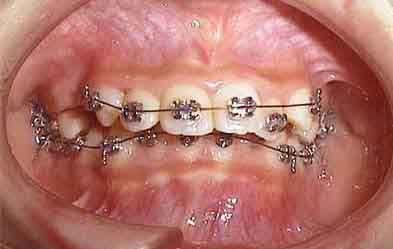

治療開始6ヶ月